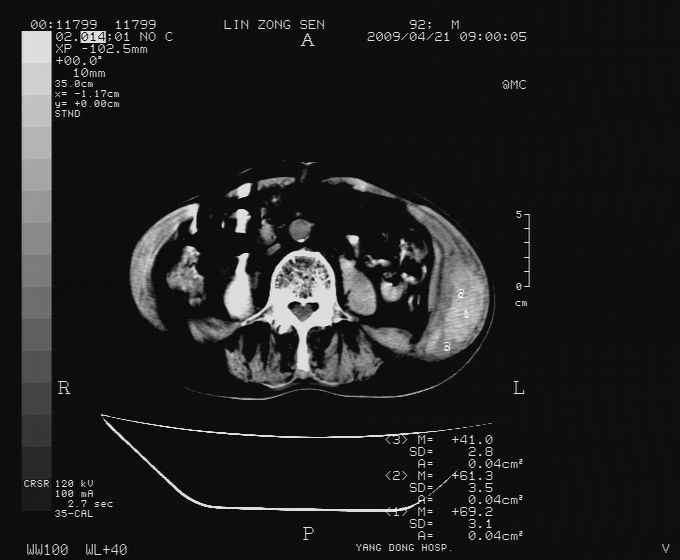

以下是引用卜一在2009-4-22 4:08:00的发言:[br]右肾积水伴输尿管上段积水!左侧肾多发囊肿!左侧腹壁软组织增厚,层次模糊,内密度较高—不排除血管瘤伴出血!